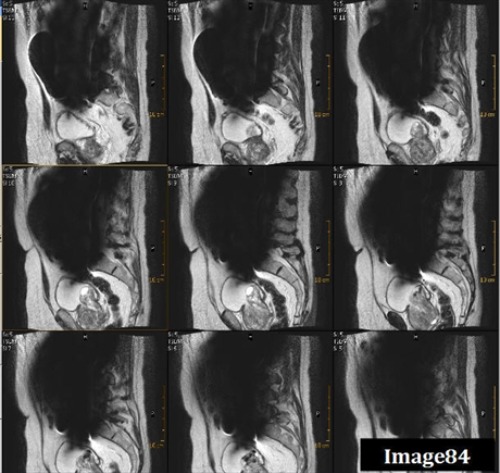

The arrows in Image 85 point to ringing lines parallel to the sharp boundary of the spinal cord. What kind of artifact is this?

A. Motion/ghosting in the phase direction

B. Gibbs truncation

C. Dielectric effects

D. RF zipper

To correct for the Gibbs truncation artifact (white arrows) seen in the spinal cord in Image 85, the technologist should:

A. Decrease phase matrix

B. Increase phase matrix

C. Increase voxel size

D. Enable flow compensation

E. Utilize gating techniques